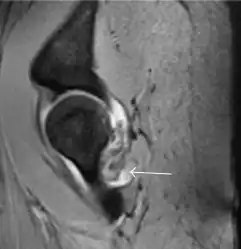

Most of the angles and measurements described in the plain radiograph section can be accurately reproduced on MRI. In addition, the superiority of MRI resolution with intra-articular contrast allows detection of labral and chondral abnormalities that may influence the choice of medical, percutaneous, or surgical management (Figure 9).[1]

Figure 9:

Sagittal T1 weighted image showing anterosuperior labral tear.[1] -

Sagittal T1 weighted image showing chondral lesion.[1] -

MR arthrography has proven superior in accuracy when compared to native MR imaging. It is considered the best technique to assess the labrum. Knowledge of the normal variable morphology of the labrum helps to differentiate tears from normal variants. A triangular shape is most commonly seen in 66% of asymptomatic volunteers, but round, flattened, and absent labra can also be found in asymptomatic populations. MR arthrography has demonstrated sensitivity over 90% and specificity close to 100% in detecting labral tears. Loose bodies are demonstrated as filling defects surrounded by the hyperintense gadolinium.[1]

Association between labral tears and chondral damage has been demonstrated. This underscores the interaction between cartilage and labrum damage in the progression of osteoarthritis. Chondral damage to the posteroinferior part of the acetabulum as a contrecoup lesion occurs in approximately one-third of pincer cases secondary to persistent abutment on the anterior part of the joint leading to a slight posteroinferior subluxation. This is considered a bad prognosis sign.[1]

MR arthrography can also demonstrate ligamentum teres rupture or capsular laxity, which are debated causes of microinstability of the hip. Elongation of the capsule or injury to the iliofemoral ligament or labrum may be secondary to microtrauma in athletes. MR can demonstrate abnormalities in these cases, such as increased joint volume or a ligamentum teres tear (Figure 9).[1]